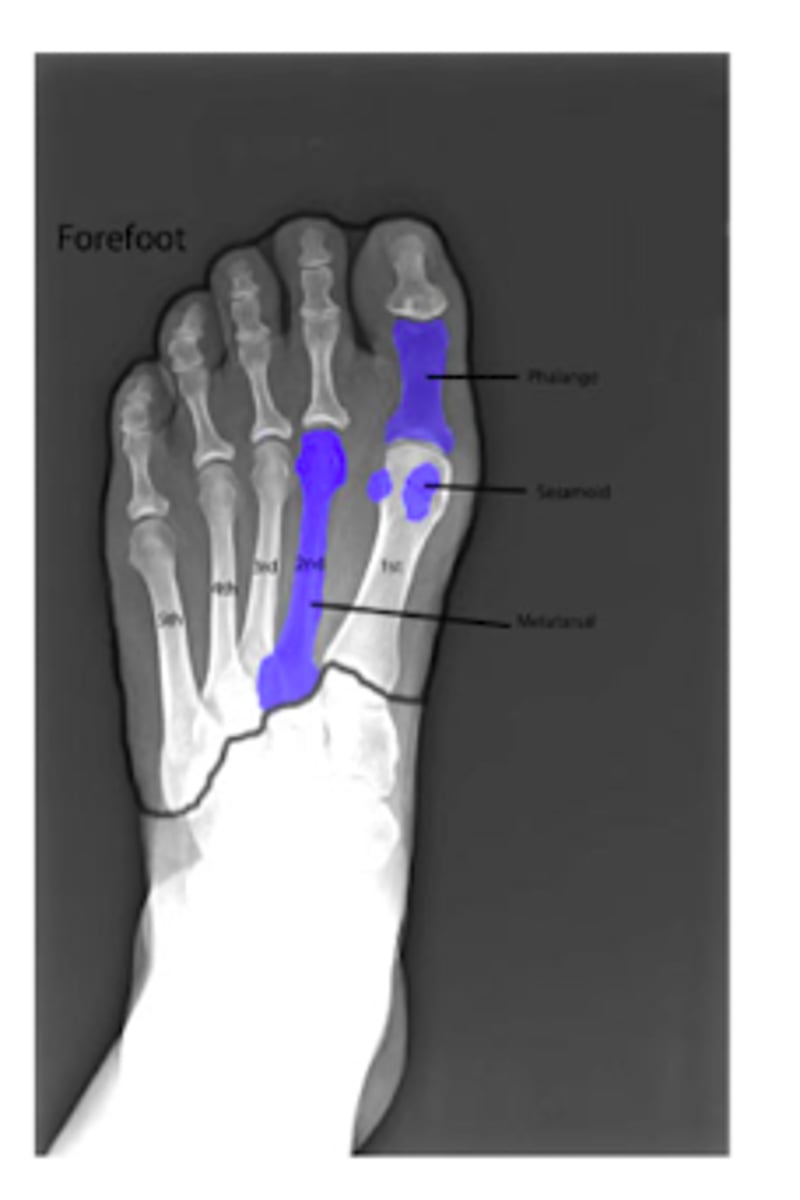

Review: Bones of the Foot.

What TWO bones comprise the FOREFOOT?

Phalanges

Metatarsals

What is fractured in the following XR?

Fracture of the 5th metatarsal is also known as what?

Jone's fracture

What is Morton's neuroma?

pinched nerve/nerve tumor in the 2/3 or 3/4 metatarsal head space